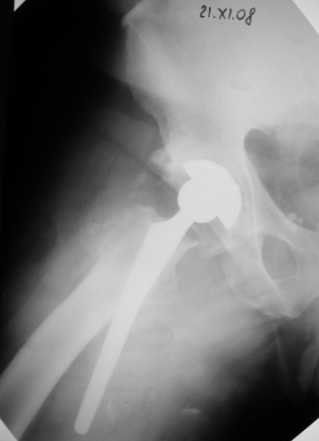

Больной Т. 56 лет, Диагноз: двухсторонний коксартроз 3-4 ст справа, 1-2 ст слева 2.10.08 выполнена операция тотальное бесцементное эндопротезирование. Использовался наружный доступ, положение на боку. Операция протекала без особенностей.

Выполнен послеоперационный ренгеноконтроль в прямой проекции. Рана зажила.

False road это ситуация случается ,в основном у начинающих. Конечно очень неприятно. В этом случае необходимо удалить протез. С удалением в такой срок - месяц-проблем не вижу. Но теперь необходим болле длинный STEM CORAIL. Такой есть у фирмы CORIN .

Уважаемый Глеб, предложенные снимки впечатлили! Никто не застрахован...

Сегодня свершилась ревизия. С максимально бережным отношением к тканям выделил бедро.

Ножка "слету " удалить не удалось, после выделения долотом ножку удалил.

Поставил Corail большего размера.

Рентгенограммы вывешу.